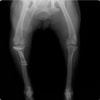

術前正面像

術前のTPAは左後肢33.1°右後肢26.8°でしたがTPLO実施により左後肢5.5°右後肢12°に矯正されました。